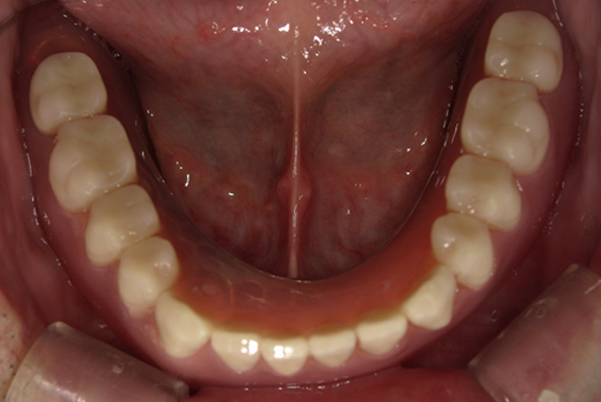

奥歯がなくなり、放置されたことで、かみ合わせが深く乱れた状態でした。

乱れたかみ合わせを治し、治療途中で見た目は患者様がご納得いく、歯の大きさ、色、形をご一緒に確認しながら入れ歯を最終的に作製しました。

-

上顎治療後

下顎治療後